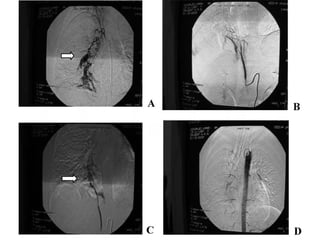

Angiografía con embolización

• diagnóstica y/o terapéutica, al permitir la embolización

de los vasos sangrantes

• La embolización selectiva puede plantearse como

tratamiento definitivo o como paso previo a la cirugía,

ya que permite al cirujano enfrentarse con un paciente

estabilizado y sin sangrado activo.

• La arteriografía bronquial se realiza mediante

cateterización arterial, generalmente transfemoral

TX. Embolizacion

TRATAMIENTO HEMOPTISIS MASIVA MedidasTransitorias Angiografía con embolización • diagnóstica y/o terapéutica, al permitir la embolización de los vasos sangrantes • La embolización selectiva puede plantearse como tratamiento definitivo o como paso previo a la cirugía, ya que permite al cirujano enfrentarse con un paciente estabilizado y sin sangrado activo. • La arteriografía bronquial se realiza mediante cateterización arterial, generalmente transfemoral

TRATAMIENTO HEMOPTISIS MASIVA Medidasdefinitivas • Hemoptisis amenazante en proceso agudo que requiere tratamiento médico (ej. TBC) • Hemoptisis amenazante en proceso, agudo o crónico, que requiere tratamiento quirúrgico (la resección quirúrgica está indicada cuando la enfermedad causante de la hemoptisis requiere de por sí tratamiento quirúrgico, esto es, en casos de enfermedad localizada técnicamente resecable y cuando no existe una alternativa terapéutica farmacológica que sea eficaz) • Hemoptisis amenazante en procesos que en principio requerirían tratamiento quirúrgico pero en los que éste está contraindicado TX. Embolizacion